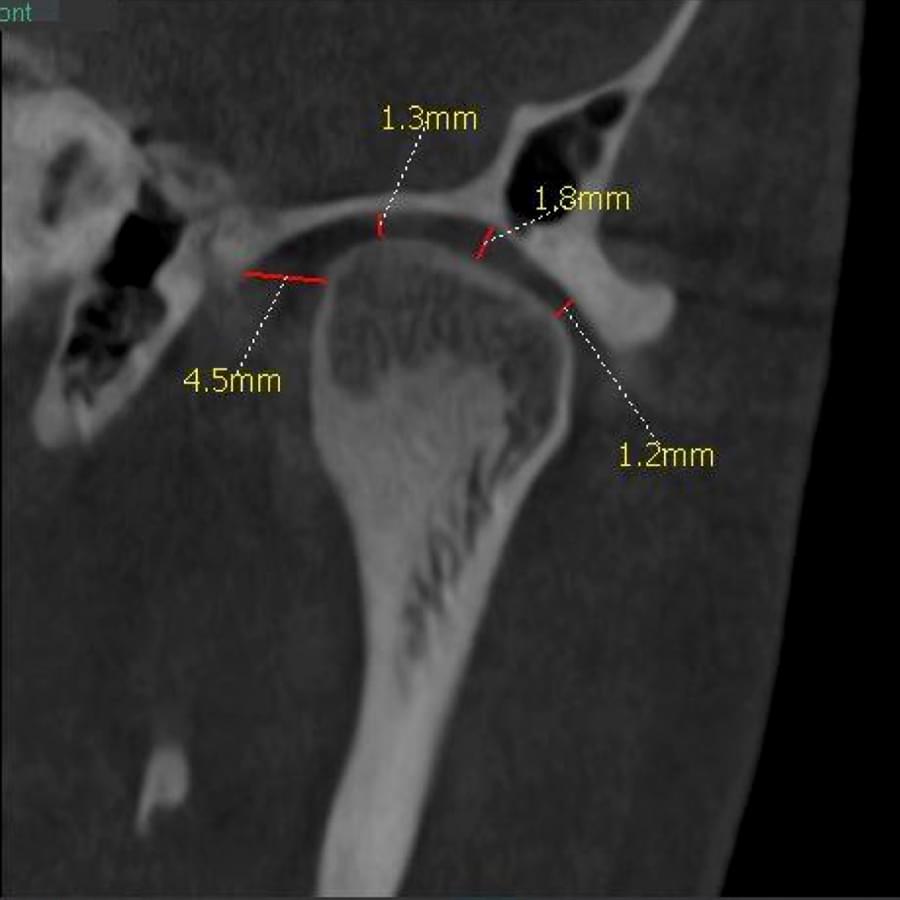

Успішна імплантація починається з бездоганної діагностики. Томограф PLANMECA забезпечує

зображення в реальному масштабі 1:1 без геометричних спотворень, що критично важливо для

вибору розміру та позиції імплантату.

Ми економимо ваш час, надаючи повний пакет передопераційної підготовки:

Детальна розмітка: промальовування нижньощелепного каналу, візуалізація синусів та

ментальних отворів.

Точні виміри: визначення висоти та ширини альвеолярного гребеня, а також оцінка щільності

кісткової тканини в зоні майбутньої операції.